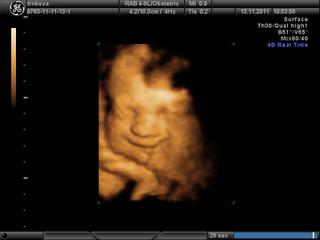

tak babule dnes nám 4D vyšlo na 100% a meno už máme dávno vybraté NINA